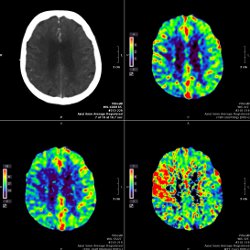

CT

Neuroradiologie